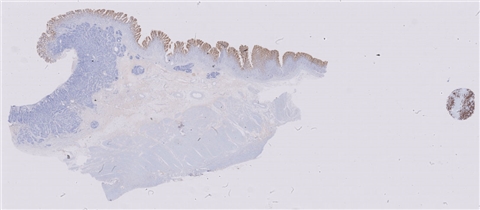

案例9 (6975)

性别:       年龄:41

患者详情: 患者于半年前无明显诱因出现大便带血,为暗红色血便,未见粘液脓血便,反复发作,无腹痛腹胀,伴大便次数增多,并大便不成形,逐渐变细,初未引起重视,亦未行相应治疗,后症状逐渐加重。为进一步诊治,2020年3月入住我院。 直肠指诊:括约肌紧张度:正常,狭窄:无,触痛:无,距离肛门口大约4cm可及一环直肠一周肿块,质硬,移动度差,无压痛,指尖稍可通过肿块,指套染血:有。 电子肠镜示:距肛门4cm直肠处可见一巨大新生物,中间凹陷,底覆污秽苔,环2/3腔生长,钳取6块送病理,余 结肠各段粘膜光整,血管纹理清晰,未见明显的溃疡、息肉。 活检病理示:恶性肿瘤。后行腹腔镜直肠癌根治术。

大体所见: 1、直肠癌肿物:已切开肠管一段,长10cm,一侧切缘周长4cm,另一侧切缘已缝合,长3cm,紧邻缝合切缘见一溃疡型肿物,大小4.5*4*3cm,肿物切面灰白灰黄色、质硬,与周围组织分界欠清,侵及全层。

2、上切缘:灰褐色黏膜组织一块,大小1*1*0.4cm。

3、下切缘:灰褐色黏膜组织一块,大小1.2*1*0.4cm。

免疫组化: 2002032-004#:CgA(弱+)、syn(+)、CD56(+)、 2002032-002#:CK(+)、TTF-1(+)、CD34 +、SMA(-)

医院: 赣南医学院第一附属医院